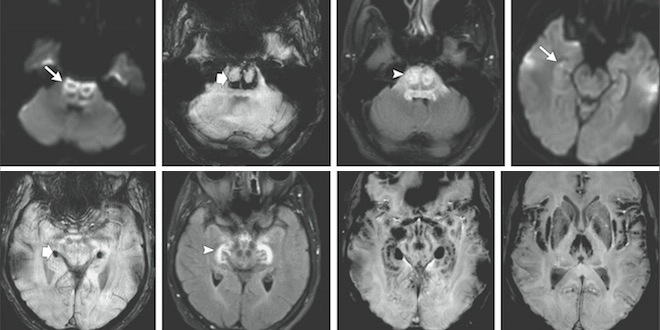

IRM cérébraux du patient décédé lors de l'essai clinique de Rennes. (doi:10.1056/NEJMoa1604221)

Dans un article publié dans la revue américaine New England Journal of Medicine (NEJM), l'équipe décrit les symptômes cliniques et les IRM du patient décédé le 17 janvier, de deux patients ayant souffert de "troubles sérieux" et d'un participant à l'essai qui n'a pas manifesté de symptômes. Les deux autres participants hospitalisés, qui avaient eux aussi manifesté des troubles sérieux, n'ont pas donné leur autorisation pour apparaître dans l'article [1].

Selon l'équipe du CHU de Rennes, les lésions cérébrales et les signes cliniques des patients hospitalisés suggèrent une "toxicité directe" de la molécule testée (BIA 10-2474), mais le "mécanisme sous-jacent" de cette toxicité "reste inconnu". Des conclusions qui rejoignent celles formulées par les experts de l'ANSM.